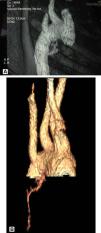

Caso clínicoNiña de 11 años que presenta emisión de sangre roja brillante por la boca, 3-4 episodios de 50ml/24h, sin antecedentes de infecciones respiratorias recurrentes ni traumatismos. Peso: 40kg (P50-75); talla: 143,5cm (P50); frecuencia cardíaca: 120 lpm; frecuencia respiratoria: 20rpm; presión arterial: 125/72 mmHg. Buen estado general. Hemodinamia, normal. Auscultación cardiopulmonar, abdomen y orofaringe, normales. Las analíticas seriadas al inicio, las 24, las 48 y las 72h posteriores fueron respectivamente: hemoglobina 13,4-12,7-11,9 y 9,3g/dl, y hematocrito de 38-37,4-34,6 y 27,3%. Las pruebas de coagulación fueron normales. La Rx de tórax al ingreso no presentó hallazgos patológicos. La fibrorrinolaringoscopia, la gastroscopia y el ecocardiograma, sin alteraciones. Evolución: en las primeras 48h persistió la hemoptisis. La angio-TC pulmonar (figs. 1–3) evidenció un tronco común con hipertrofia de arteria bronquial derecha originada en el arco aórtico adyacente en el origen de la subclavia derecha aberrante e imagen alveolar en base derecha. Se realizó una embolización endovascular selectiva (fig. 4) y una fibrobroncoscopia en el mismo acto. Se cateterizó, a través de vía femoral, la arteria bronquial de origen anómalo con hipervascularización patológica de lóbulo inferior derecho. Se utilizaron microesferas de 500-700μm en el procedimiento de embolización, con resultado satisfactorio.

En nuestra paciente, el hemograma seriado durante 48h objetivó descenso de 3g/dl de hemoglobina, sin alteraciones en las pruebas de coagulación, y la paciente permaneció hemodinámicamente estable. La angio-TC identificó la arteria bronquial derecha hipertrofiada con origen anómalo en el arco aórtico adyacente a subclavia derecha aberrante (fig. 2).

La TC ha demostrado ser de gran valor diagnóstico para determinar la causa fundamental, pudiendo localizar la fuente del sangrado en el 63-100% de los casos16. La angio-TC puede evidenciar los sistemas arteriales bronquiales y no bronquiales, y detectar lesiones vasculares17. La TC multidetectora es una técnica de imagen que reproduce imágenes de amplio rango anatómico, reduciendo el tiempo de exposición y los artefactos debidos a movimientos respiratorios. Realizada con contraste, obtiene estudios de alta resolución de imágenes multiplanos reformateadas. En la práctica, la angio-TC con contraste es la prueba diagnóstica más sensible, capaz de representar un trazado de los vasos torácicos, ubicar el lugar del sangrado y la patología subyacente4,5,17–19. La información que aporta fundamenta la planificación de la embolización. El estudio de Remy- Jardin et al17 describe que la angio-TC proporciona mayor información que la angiografía convencional en relación con los sistemas arteriales bronquiales y no bronquiales, e igualmente se ha comunicado que es capaz de detectar el 100% de las arterias bronquiales y el 62% de las arterias no bronquiales causantes de hemoptisis18.